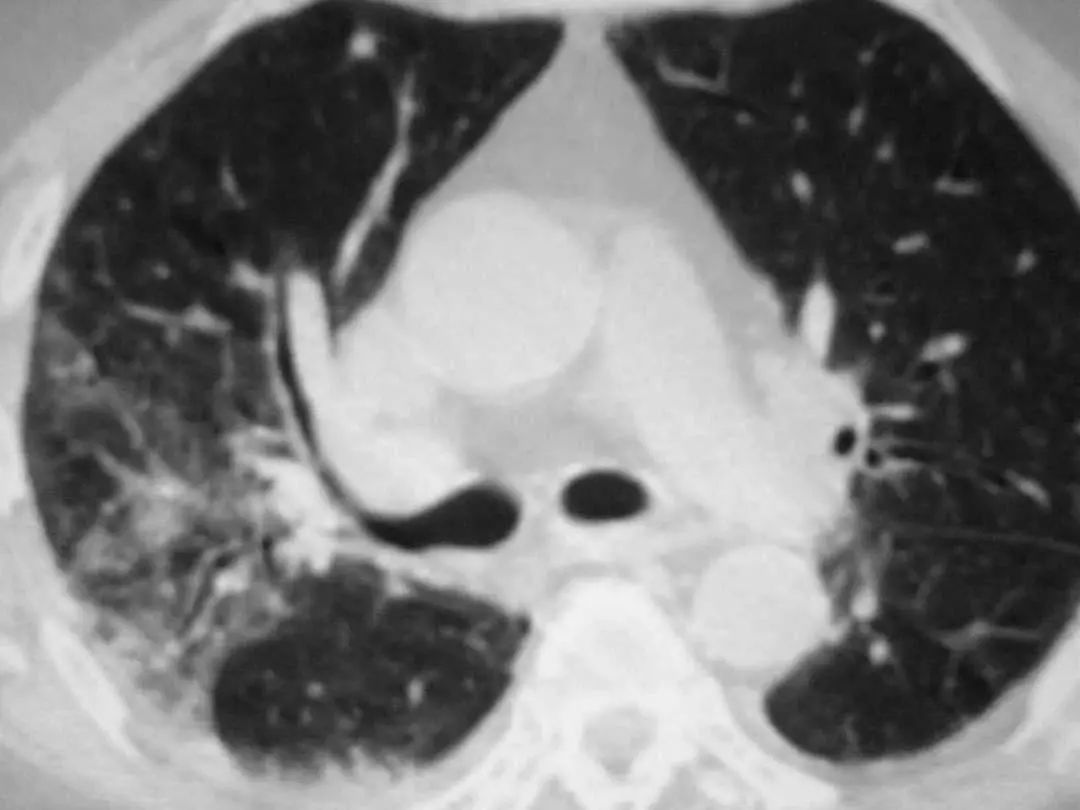

图1.4 53岁的严重军团菌肺炎患者。胸片显示双肺下叶致密实变。

图1.5 40岁肺炎衣原体患者。胸片显示右上、中、下叶多灶性斑片状实变。